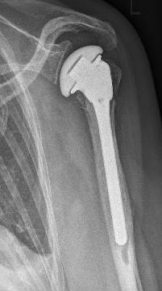

One possibility of surgical therapy is stabilization with a stable-angle plate In addition, with the frequent form of subcapital humeral fracture, a nail can be inserted into the upper arm and the fracture can thus be splinted from the inside. In case of severe damage, the humeral head may have to be replaced by a prosthesis.

Proximaler Oberarmbruch9Proximaler Oberarmbruch10

Picture: A subcapital upper arm fracture was treated with a prosthesis. The humeral head was completely removed and replaced by the prosthesis. This is anchored in the upper arm with the prosthesis shaft.